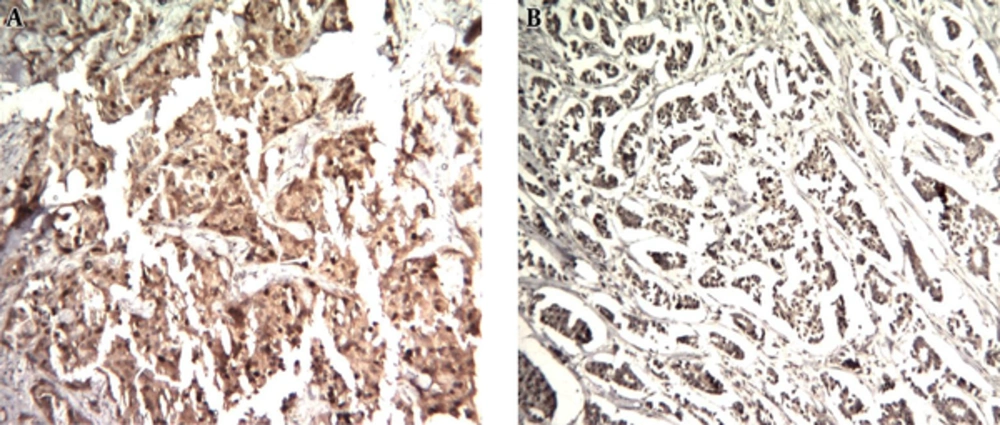

4.1. MAGE-1 Cytoplasmic Expression

One hundred and thirteen samples were examined for cytoplasmic MAGE-1 expression by IHC. Table 2 summarizes IHC staining results. MAGE-1 expression (score ≥ 2+) was detected in 34/111 (30.1%) of patients (Figure 1).

4.2. MAGE-1 Nuclear Expression

One hundred and thirteen samples were examined for nuclear MAGE-1 expression by IHC. Table 2 summarizes IHC staining results. MAGE-1 expression (score ≥ 2+) was detected in 36/111 (31.8%) of patients (Figure 1).

MAGE-1 cytoplasmic expression (score ≥ 2+) was detectable in 30.1% and nuclear expression (score ≥ 2+) was detectable in 31.8% of patients.